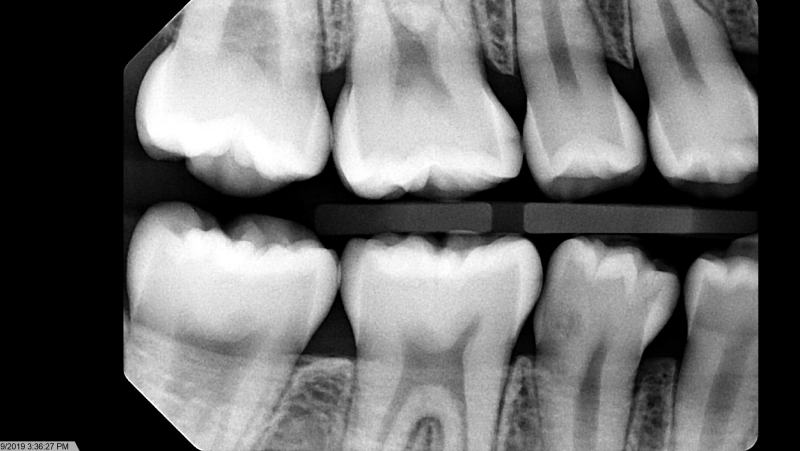

Case: RCT on Tooth #8,9

49-year-old male, chronic abdominal pain, history of small bowel obstruction ×4, gastritis (treated), colitis, on famotidine. NKDA.

Dx: Symptomatic irreversible pulpitis (#8, #9); normal apical tissues.

Tx: Root canal therapy due to pulpal exposure from severe occlusal wear.

Reflection

Restoring these teeth was questionable due to severe wear and limited vertical space. It was important to set expectations about the risk of not being able to place crowns afterward. The patient was still motivated to keep the teeth and chose RCT over extraction.